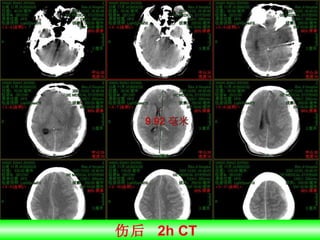

伤后  2h CT